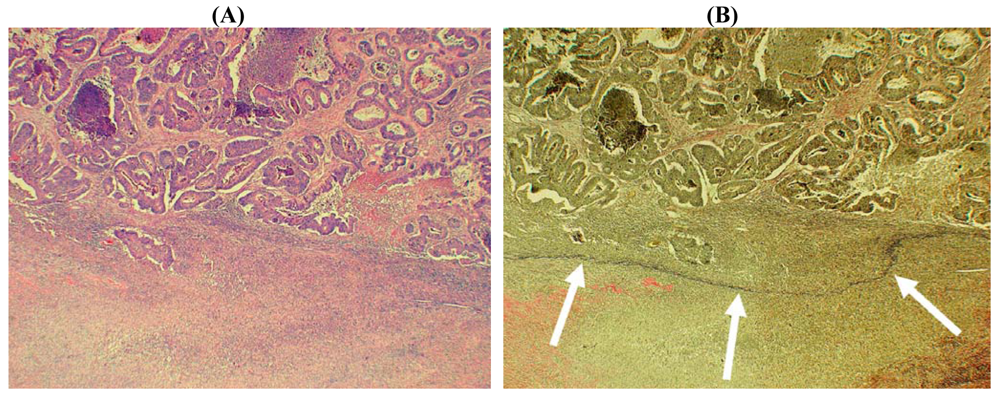

The final technique that might prove helpful in the evaluation of potential serosal invasion is based upon the immunohistochemical demonstration of mesothelial cells. Immunohistochemistry has the advantage of offering relatively cell-type specific labeling and, therefore, in theory could highlight residual mesothelium (and hence the serosal surface) when this is inconspicuous using routine hematoxylin and eosin (H&E) staining. Several ‘mesothelial markers’ including calretinin, D2-40/podoplanin, WT1 and cytokeratin (CK) 5/6 are used routinely in diagnostic histopathology practice, but in our experience CK7 staining is often most useful in this context since it labels mesothelial cells strongly whereas reactive stromal elements and tumor cells in the majority of CRC are negative. We have found that CK7 staining is particularly useful in demonstrating the deep serosal clefts that are easily overlooked on routine staining, and the presence of tumor cells invading and disrupting the mesothelium confirms the presence of serosal invasion (Figures 5 and 7). However, to our knowledge no studies to date have formally assessed the value of mesothelial cell immunostaining as an adjunct marker in the assessment of CRC.